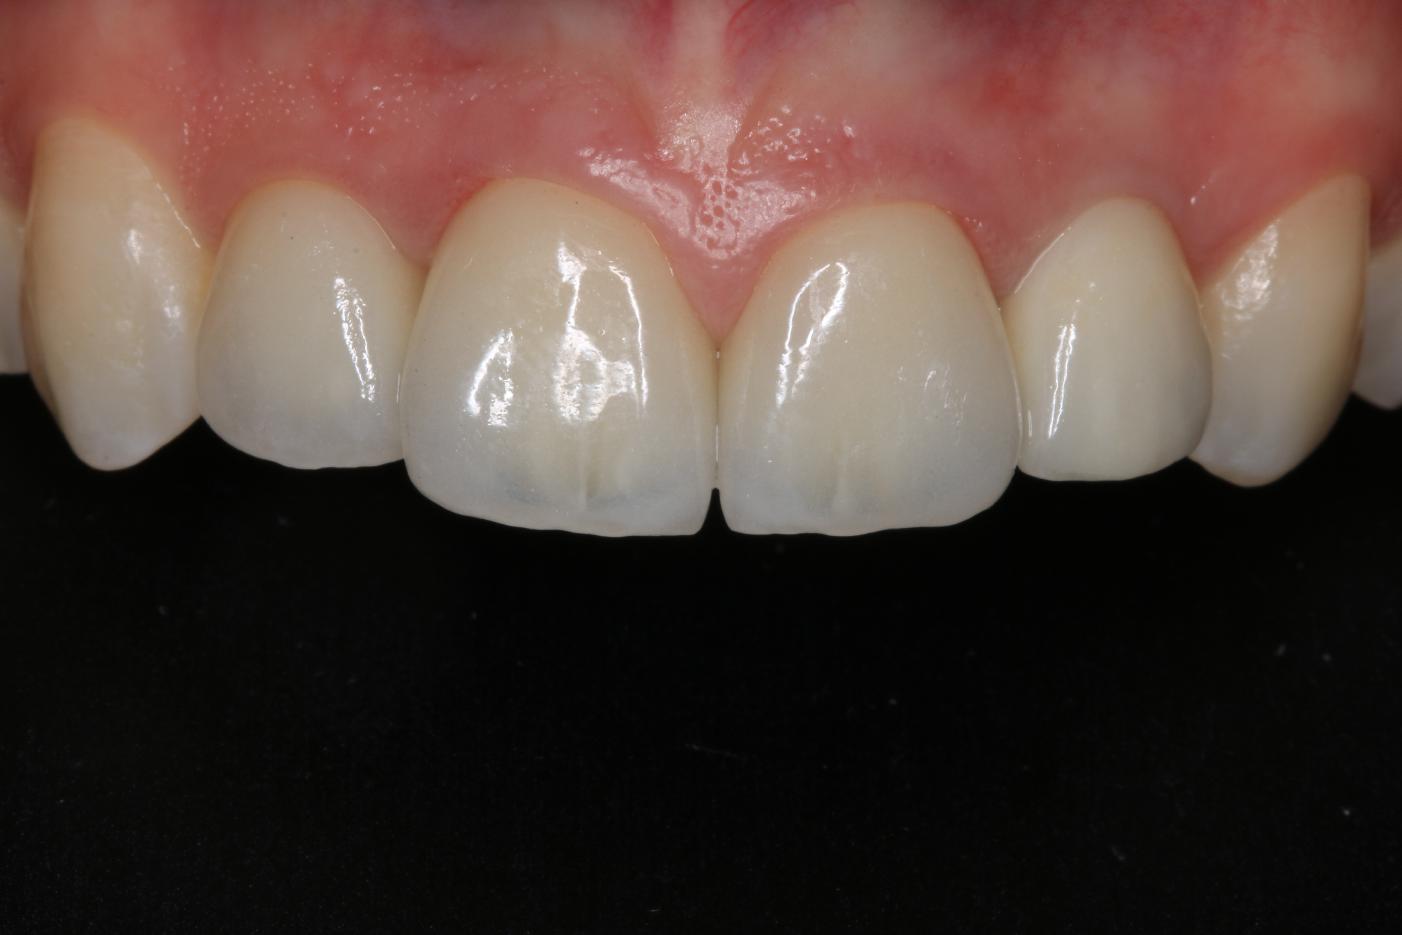

10/12 - Clinical outcome with prosthetics 6 months post-operativeSoft tissue thickening at immediate implant placement and GBR with mucoderm® and maxgraft® - Dr. A. Puisys